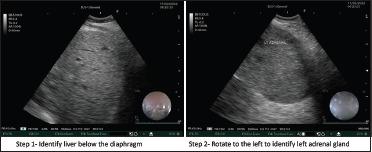

Endobronchial ultrasound-guided transbronchial needle aspiration (EBUS-TBNA) is a standard-of-care modality for evaluating mediastinal lymph nodes and masses. The EBUS bronchoscope may also be introduced through the oesophageal route to perform sampling of accessible lesions, a technique described as transoesophageal bronchoscopic ultrasound-guided fine-needle aspiration (EUS-B-FNA). Because of the central oesophageal approach, EUS-B-FNA provides easy access to the left para-tracheal, subcarinal and para-oesophageal lymph nodes. In addition, the left adrenal gland (LAG) can also be imaged and sampled during the EUS-B-FNA procedure. In patients with suspected lung cancer, accurate staging is essential. Adrenal metastasis is relatively common and may often be a solitary metastatic site. We describe three cases where EUS-B-FNA was performed to safely sample the enlarged LAG in suspected lung cancer. We also review the literature on the performance characteristics of EUS-B-FNA for LAG aspiration.

支气管内超声引导下经支气管针吸活检术(EBUS-TBNA)是评估纵隔淋巴结和肿块的标准治疗方式。EBUS支气管镜也可经食管途径插入,对可触及的病变进行采样,该技术称为经食管支气管镜超声引导下细针穿刺活检术(EUS-B-FNA)。由于采用经食管中心入路,EUS-B-FNA能够轻松到达气管旁左侧、隆突下及食管旁淋巴结。此外,在EUS-B-FNA操作过程中,还可对左肾上腺(LAG)进行成像和采样。在疑似肺癌患者中,准确分期至关重要。肾上腺转移相对常见,且常可能是唯一的转移部位。我们描述了3例通过EUS-B-FNA对疑似肺癌患者肿大的LAG进行安全采样的病例。我们还回顾了关于EUS-B-FNA对LAG穿刺活检性能特征的文献。